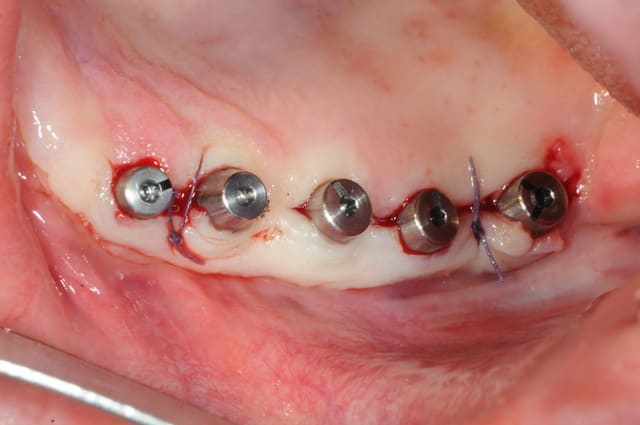

non pas 2 mais 4 implants en difficultés (très peu mobiles, mais quand même), et puis surtout une grosse fonte osseuse sur plusieurs spires. la fonte prend la forme d'une cuvette.

donc dépose, curetage, pose d'implants de diamètre plus importants ,mise en place Bio-Os et membrane Bio Gide

Ton lambeau a une forte épaisseur comme dans les cas ou cela m est arrive et j émets l hypothèse d' une mise en charge précoce des implants a cause des tensions lors de sutures génère par le dépassement de la vis de couv

Chose que l'on n a pas lors Dun implant en un temps ou lorsque les vis n émergent pas du fut

D57, ton os n'a visiblement pas une "qualité" top...je maintien mon avis que c'est un problème de contraintes transmises à l'os par l'implant, entraînant une lyse osseuse plutôt qu'une ostéointégration...